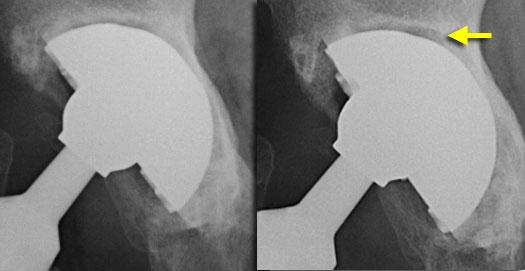

Eccentric position of femoral head within cup consistent with polyethylene wear.Focal osteolysis with endosteal scalloping in proximal femur due to particle disease.

Particle Disease

Ban đầu bệnh lý này được gọi là bệnh xi măng hoặc u hạt xâm lấn.

Đây là phản ứng mô bào xảy ra do phản ứng của đại thực bào với bất kỳ thành phần nào bong tróc khỏi bề mặt các cấu kiện của khớp nhân tạo.

Ngày nay, bệnh lý này chủ yếu gặp ở khớp háng không xi măng như một phản ứng với các hạt mài mòn polyethylene nhỏ.

Trên hình ảnh X-quang, các tổn thương u hạt xâm lấn này biểu hiện dưới dạng các vùng thấu quang khu trú xung quanh khớp nhân tạo.

Tình trạng này có xu hướng xảy ra trong khoảng từ 1 đến 5 năm sau phẫu thuật và liên quan đến hình ảnh lõm vỏ nội tủy nhẵn.

Đặc điểm then chốt là bệnh lý này không tạo ra phản ứng xương thứ phát.

Những đặc điểm này giúp phân biệt bệnh hạt nhỏ với nhiễm trùng, vốn thường có các biểu hiện xâm lấn hơn, mặc dù việc phân biệt không phải lúc nào cũng khả thi.

Mặc dù bệnh hạt là kết quả của sự mài mòn polyethylene, nhưng không phải lúc nào bạn cũng thấy các dấu hiệu rõ ràng của sự mài mòn polyethylene ở ổ cối nhân tạo.

Tuy nhiên, bất cứ khi nào thấy vị trí lệch tâm của chỏm xương đùi trong ổ cối, hãy tìm kiếm các vùng thấu quang khu trú.

Các khuyết hổng khu trú lớn có thể được phát hiện trong khi khớp nhân tạo vẫn còn vững.

Bệnh hạt tiến triển không ngừng với tình trạng lỏng khớp, gãy xương và phá hủy xương.

Đôi khi cần phải phẫu thuật thay lại một khớp háng toàn phần còn vững vì nếu mất xương nhiều hơn sẽ khiến phẫu thuật thay lại trở nên không thể thực hiện được.

Subtle eccentric position of femoral head. Even more subtle focal osteolysis around screw in acetabulum.

Bệnh do hạt mài mòn (2)

Các hạt mài mòn nhỏ từ lớp lót polyethylene được bong ra vào dịch khớp và có thể di chuyển xung quanh khớp giả thông qua các kênh nhỏ ngay cả ở những khớp háng còn vững.

Chúng có xu hướng di chuyển qua các lỗ vít (hình minh họa).

Đây là lý do tại sao các phẫu thuật viên ngày càng hạn chế sử dụng vít để cố định cốc acetabulum.

Một trường hợp khác ở bên trái.

Một lần nữa có hiện tượng tiêu xương khu trú xung quanh các vít sau khi các hạt mài mòn di chuyển qua các lỗ vít.

Vị trí lệch tâm của chỏm xương đùi trong ổ cối nhân tạo do mòn polyethylene.